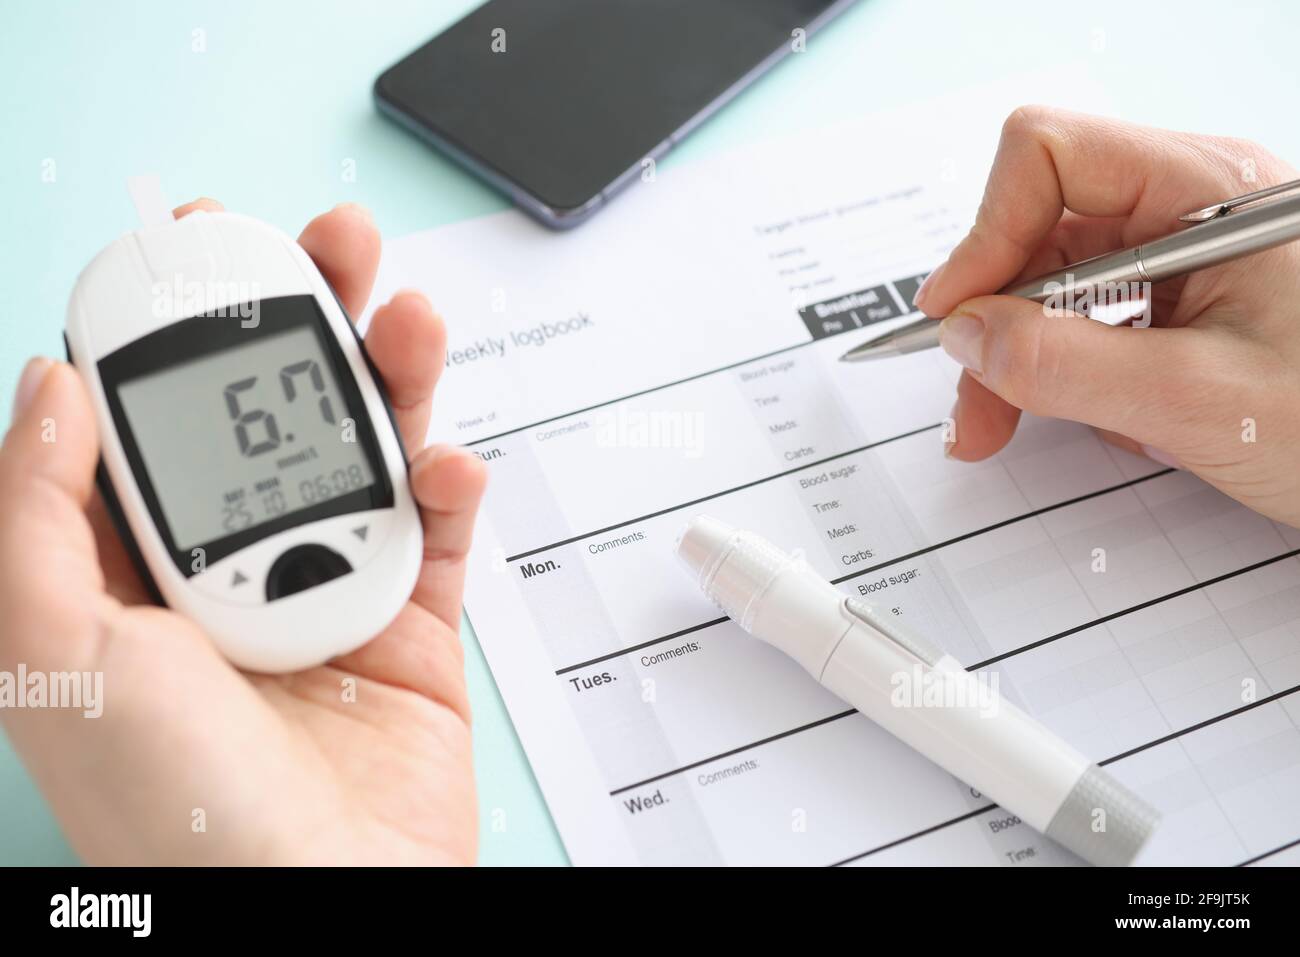

Patient holding glucometer and recording data in diary closeup Stock Photohttps://www.alamy.com/image-license-details/?v=1https://www.alamy.com/patient-holding-glucometer-and-recording-data-in-diary-closeup-image418994847.html

Patient holding glucometer and recording data in diary closeup Stock Photohttps://www.alamy.com/image-license-details/?v=1https://www.alamy.com/patient-holding-glucometer-and-recording-data-in-diary-closeup-image418994847.htmlRF2F9JT5K–Patient holding glucometer and recording data in diary closeup